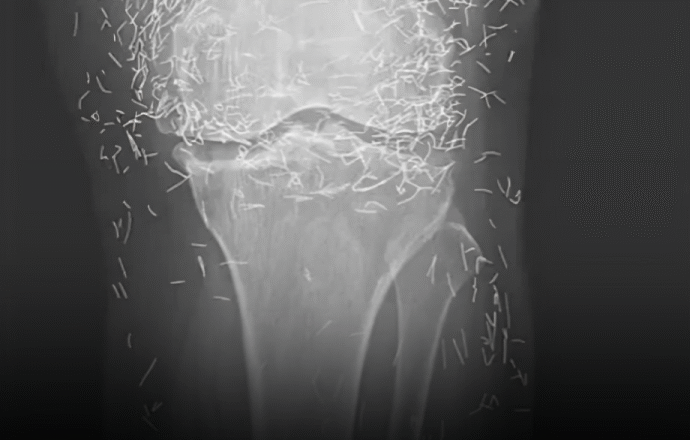

Коли лікарі досліджували рентгенівський знімок колін літньої жінки, яка страждала від сильного болю в суглобах, вони знайшли золоту жилу: сотні крихітних золотих голок для акупунктури, залишених у її тканинах.

У звіті йдеться, що під час лікування жінки акупунктурою голки, які, ймовірно, були виготовлені з золота, були навмисно залишені в її тканинах для подальшої стимуляції.

Це також може ускладнити для лікаря читання рентгенівського знімка. «Голки можуть приховувати деякі анатомічні органи», – сказав Гермазі.